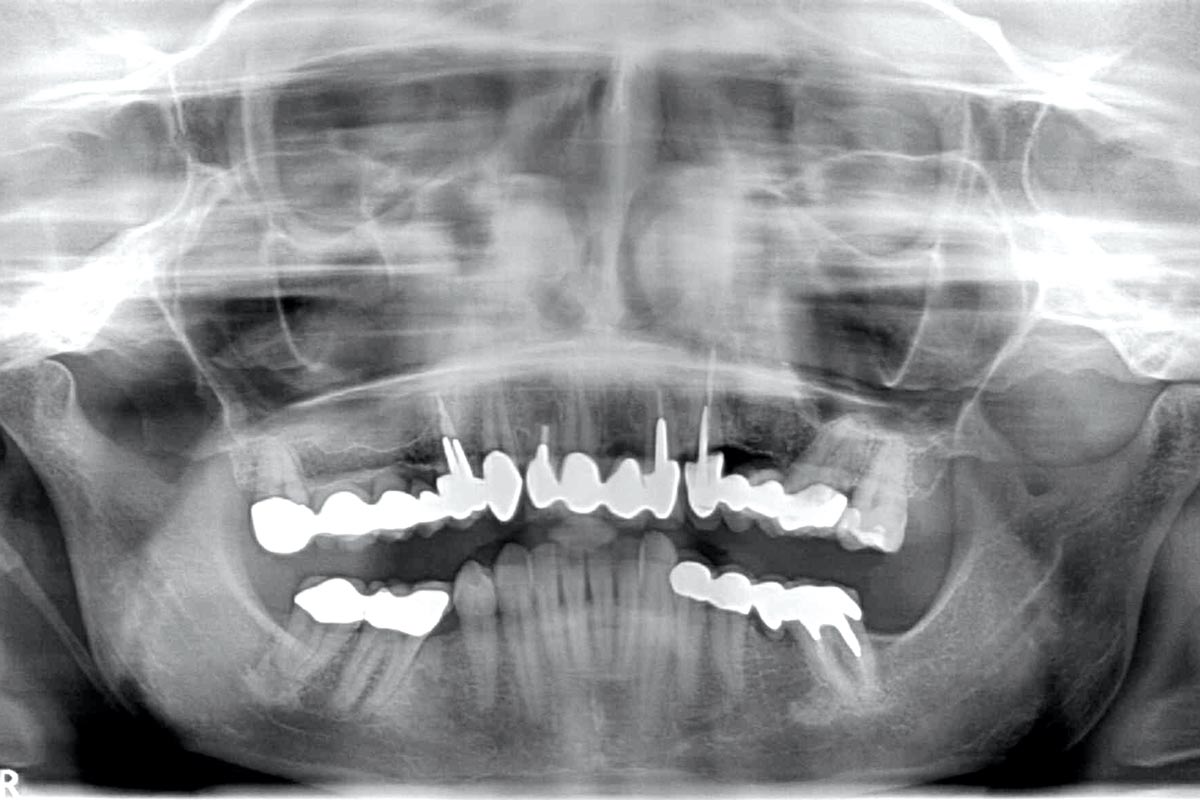

Regeneration of a 9 mm vertical bone defect with cerabone®, autologous bone and S-PRF –  Dr. A. Eslava